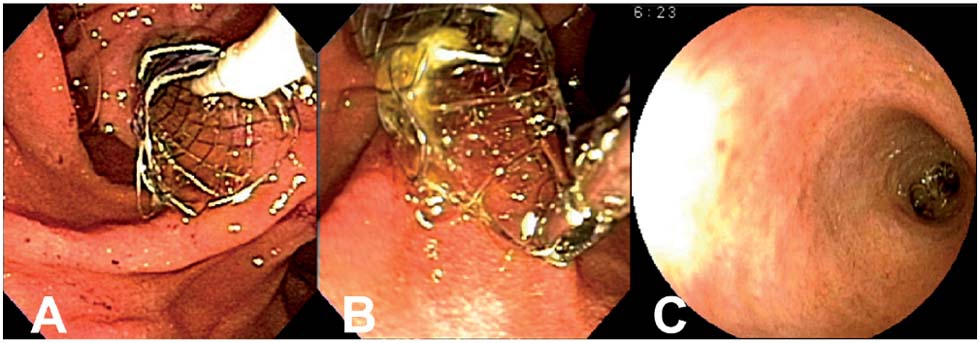

Sphincterotomie Endoscopique Et Pose De Prothese Dans Une Tipmp Symptomatique Avec Pancreatite Sfed